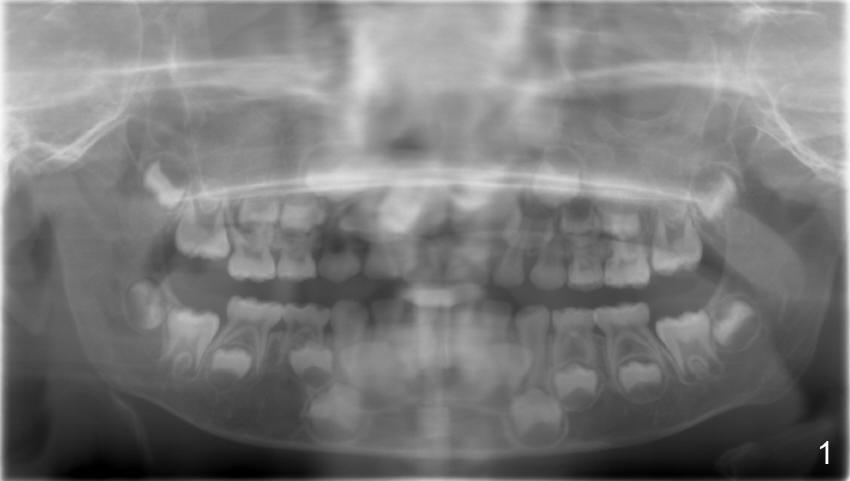

Eight-year-four-month-old boy shows early signs of Class II Division I malocclusion (Fig.2-5).  Panoramic X-ray was taken when he was 5 years 10 months old (Fig.1).

-Watch the erupting #6 on a future panorex compared to this one.